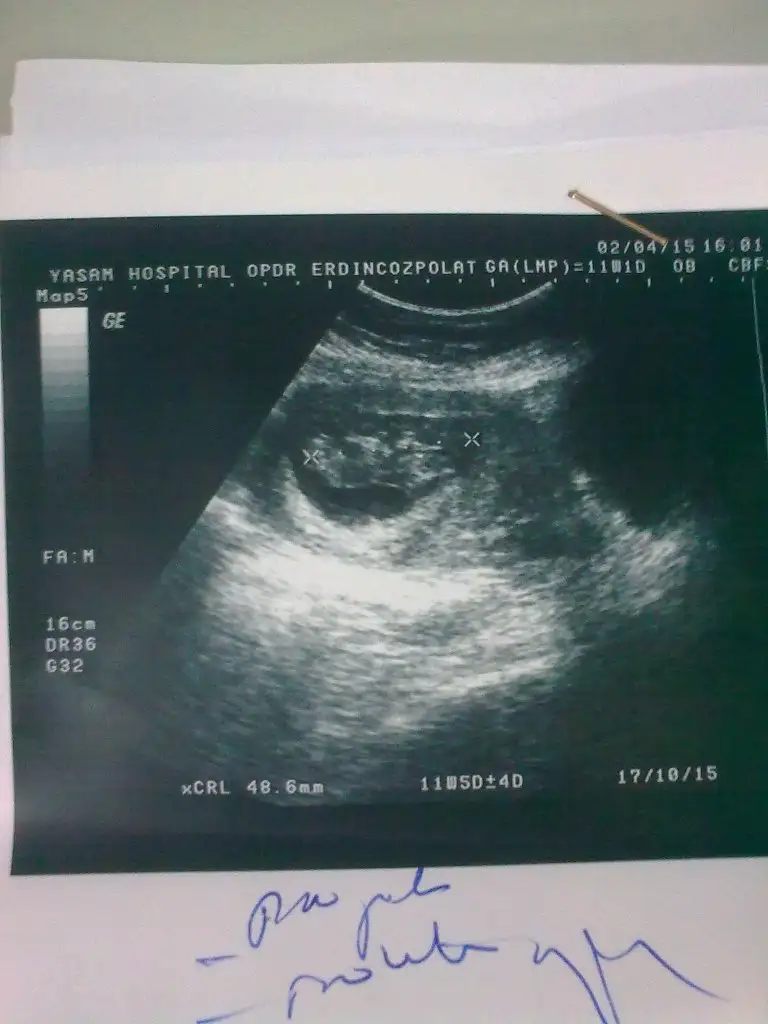

Kızlar çok yoğunum yazamıyorum kusura bakmayın. Hamile olan goamıydı hayırlı olsun Rabbim gönlüne göre versin inşallah. Kese fotosu atan eyhammıydı bebeği keseye göre erkek kese içinde sağda bebek çünkü. Bu dr remzi teorisiymiş. Test atan arkadaş inan testlerden anlamıyorum ama testte hata daha yüksek bence ağrı ve ateşe göre yaptıysan daha mantıklı yapmışsın. Asosyalci bebeğin foto koy bakalım belki biz yorum yaparız. Şuan okadar yoğunum isimler vs karıştı ama neyi kime yazdığımı anlar herkes inşallah

Eklentiler

• Görüntü1879.webp

Görüntü1879.webp

21,5 KB · Görüntüleme: 150